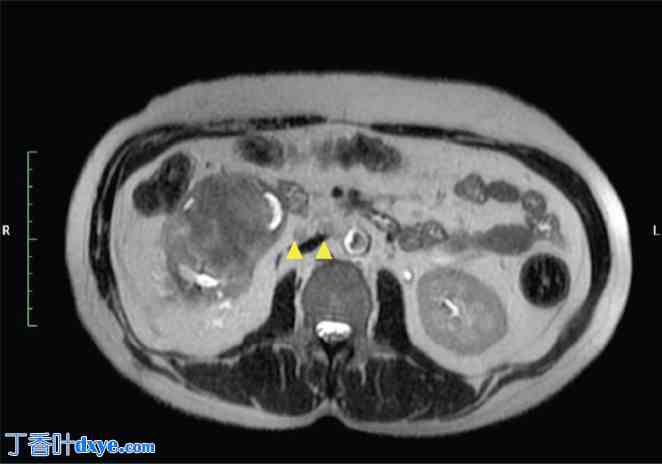

一位54岁男性患者,既往无其他疾病,因右侧腰痛就诊。非增强CT检查证实其肾盂内有鹿角状结石,未见可疑肿块。随后,患者接受了两次经皮肾镜取石术(PCNL),直至结石完全取出。术后3个月,患者持续出现右侧腰痛和偶发性血尿,遂转诊至院。进一步行增强CT和磁共振成像(MRI)检查,发现右肾内存在一强化病灶,从肾盂延伸至PCNL手术通道,并伴有腔静脉后、主动脉腔静脉和腔静脉前淋巴结肿大(图1-4)。CT引导下穿刺活检证实为高级别鳞状分化癌。血尿素氮为30 mg/dL,肌酐为1.2 mg/dL,钙为9.2 mg/dL,磷酸盐为3 mg/dL。尿细胞学检查发现发育不良细胞,二乙烯三胺五乙酸(DTPA)检查显示患侧肾脏肾小球滤过率降低至20 mL/min,未见其他部位转移。因此,患者接受了根治性肾切除术,同时整块切除了两个经皮肾镜取石术(PCNL)通道、受累皮肤和侧腹肌,并进行了基于模板的腹膜后淋巴结清扫术,随后进行了网片重建。术后恢复顺利。最终的组织病理学检查结果显示,肾脏大小为15 × 8 × 8 cm,输尿管长12 cm,以及两块分别包含下方PCNL通道的皮肤,大小分别为8 × 3.5 × 5 cm和5 × 2.5 × 2 cm。显微镜检查显示肿瘤从肾盂浸润,穿过肾周脂肪组织延伸至经皮肾镜取石术(PCNL)通道直至皮肤,组织学特征提示为2级鳞状细胞癌(SCC)。所有切缘均未见肿瘤残留,也未见淋巴血管或神经周围浸润的证据。此外,29个清扫的淋巴结均未见转移。患者接受了辅助放疗,照射范围包括肿瘤床和腹主动脉旁淋巴结区域,总剂量为50.4 Gy,分28次完成。此外,患者还接受了为期12周的化疗,每周一次,方案为紫杉醇80 mg/m²联合卡铂(AUC 2)。随访2年后,患者仍无复发。

图 4. MRI T2 轴位图像显示右肾门淋巴结(黄色箭头)。

4.jpg